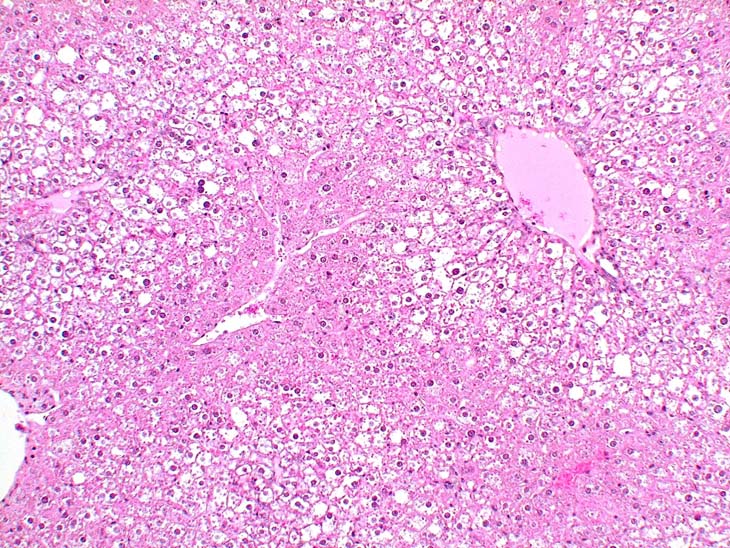

Glycogen rich hepatocytes are localized in periportal and mid-lobular areas of the liver of this untreated male B6C3F1 mouse.